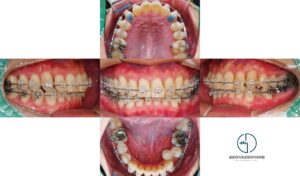

중화동 치과 삐뚤어진 앞니, 윗니만 치료하고싶어요, 미니튜브를 이용한 상악 부분교정

안녕하세요, 중화동 치과 김정은 원장입니다. 교정 치료라고 하면 흔히 위아래 치아 전체에 장치를 붙이고오랜 시간 치료하는 모습을 떠올리기 쉽습니다. 하지만 교정은 치아 상태와 목적에 따라 전악 교정이 필요한 경우도 있고일부…